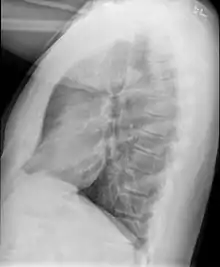

Medical imaging

Early in the disease chest radiography is typically normal but may show hyperinflation.[6] As the disease progresses a reticular pattern with thickening of airway walls may be present.[4][6] HRCT can also show air trapping when the person being scanned breathes out completely; it can also show thickening in the airway and haziness in the lungs.[11] A common finding on HRCT is patchy areas of decreased lung density, signifying reduced vascular caliber and air trapping.[6] This pattern is often described as a "mosaic pattern", and may indicate bronchiolitis obliterans.[6]